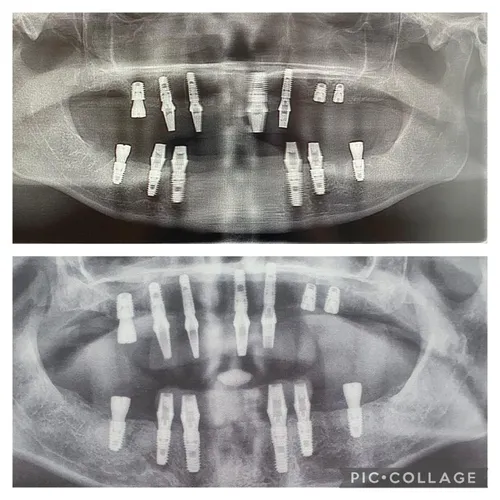

Britanka (40) kaže da su joj dva dentalna implantata, ugrađena u Turskoj, probila sinuse i nosnu šupljinu, zbog čega joj je lice deformirano, a svakodnevno trpi jake bolove.

Privatni stomatolog ustanovio je da su dva implantata probila sinusnu i nosnu šupljinu. Sada joj prijeti kompletno uklanjanje svih implantata, a trošak novog zahvata mogao bi doseći 45.000 funti.

Prema njezinim riječima, stomatolog joj je preporučio podizanje sinusa, koštane transplantate te ukupno 15 implantata – osam u gornjoj i sedam u donjoj čeljusti.